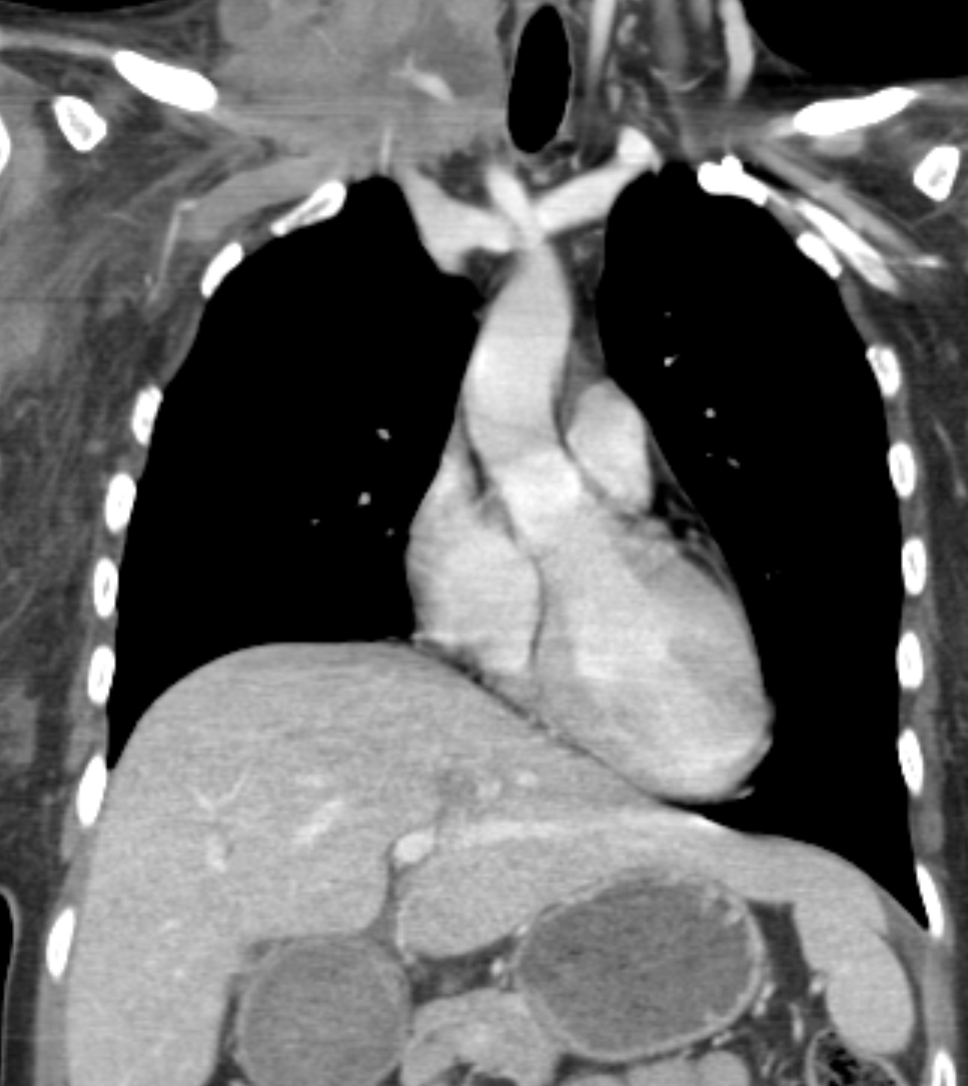

lymphoma coronal CT

Rt supraclavicular nodes - coronal CT